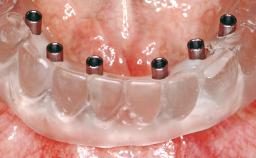

| # of Implants | 8 |

| Attachment | One-Piece |

| Abutment Type | Standard |

| Prosthesis Type | FDP |

| Loading Protocol | Conventional or early |